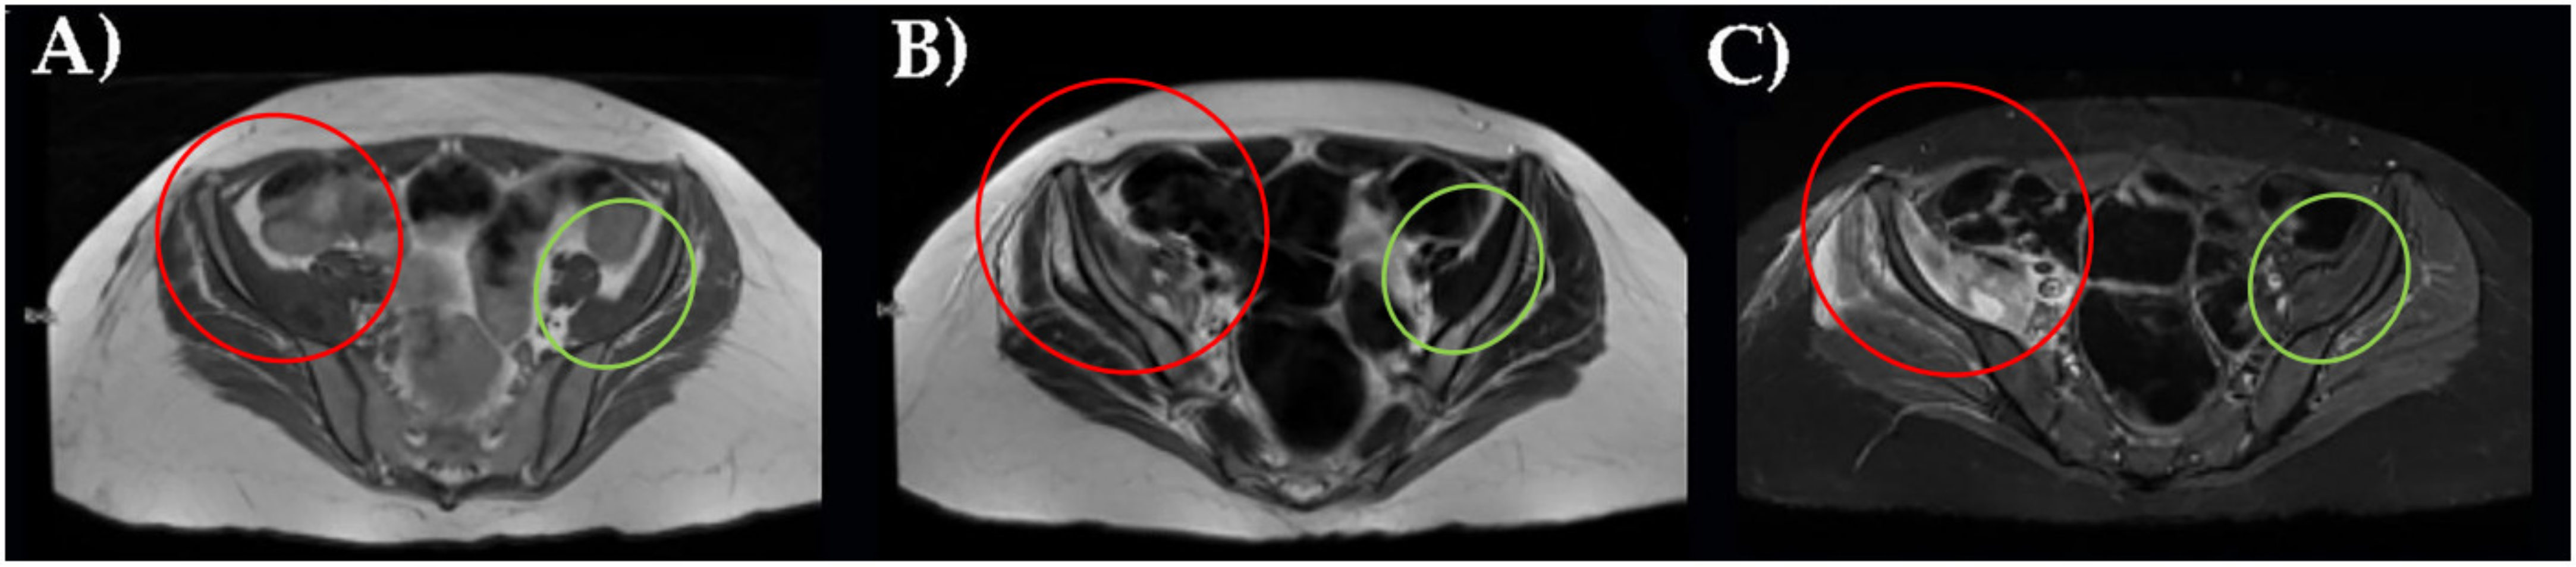

Three different instrumental imaging examinations were performed. An ultrasound study excluded a peritoneal effusion but was not more informative for extensive meteorism. CT without contrast revealed an enlargement of right iliac muscle, slightly parenchymal inhomogeneity without signs of overt bleeding and excluded other causes of leg pain (Figure 1).

Figure 1. CT axial scan of the pelvis with right ileal muscle hematoma. (A). CT coronal scan of the pelvis with right ileal muscle hematoma (B). In red, pathological finding; in green, normal appearance.